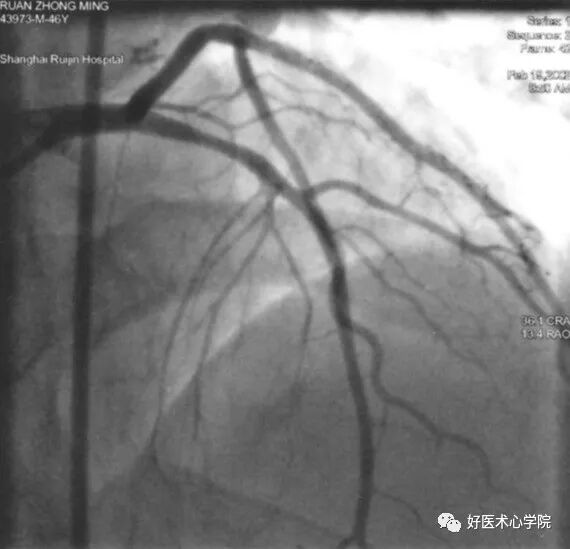

左冠造影体位

左肩位:非常清楚的显示前降支中远段和对角支中远段,及前降支和对角支分叉处。